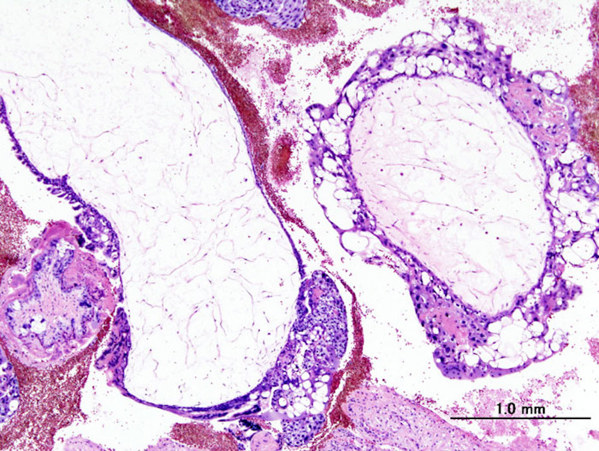

Sometimes an egg loses its DNA. When that egg is fertilized by a sperm, a molar pregnancy is the result. Molar pregnancy can also be called a hydatidiform mole (that's a tongue twister!).5

Because all the DNA is from the father, the pregnancy isn't normal. There is some growth of the placenta. The embryo, however, develops very little or not at all. A molar pregnancy can, in a few cases, also become a cancer.5